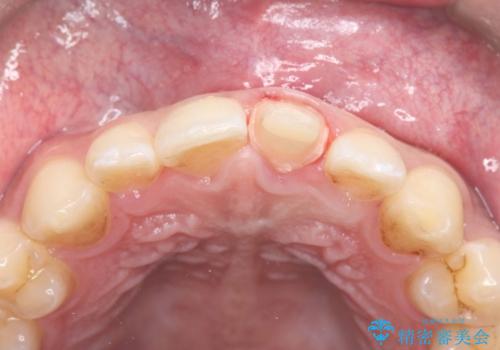

- 歯冠破折により点状露髄を認めました。破折から1週間以内であったこと、また歯髄診断により生活反応が良好で保存可能と判断したため、VPT(生活歯髄療法)を行い神経の保存を試みました。

神経の状態が良好に保たれていることを確認した後、オールセラミッククラウンによる審美修復を行いました。